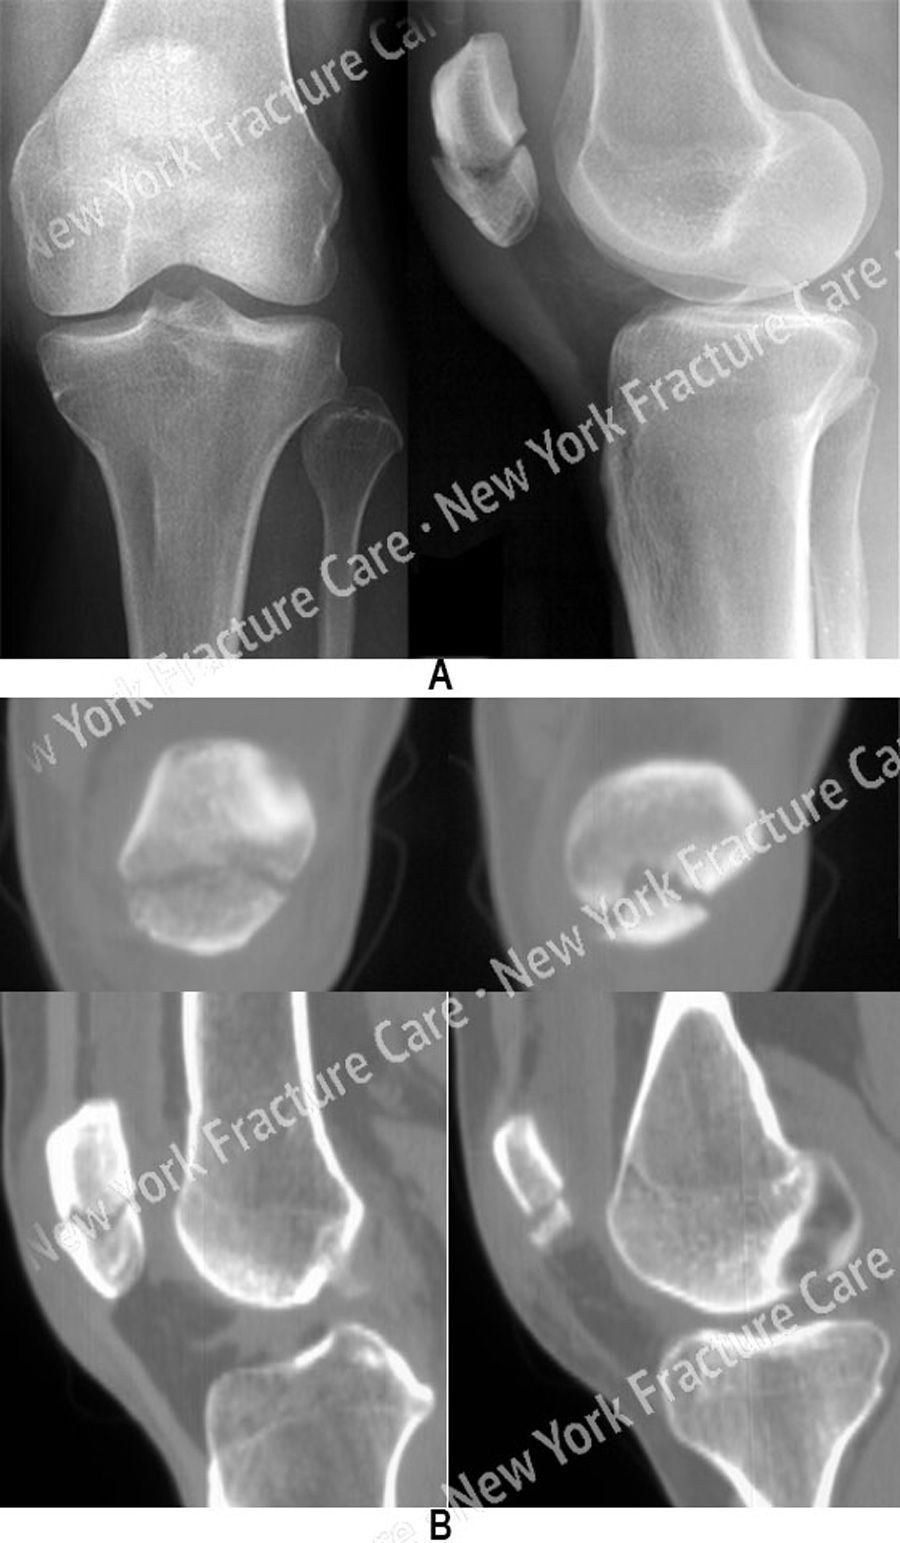

Recovery time for fractured patella General center. If your fractured patella was treated without surgery, you can expect your initial recovery time to take about four to six weeks. This is how long it usually takes any broken bone to heal, and you'll likely be wearing a cast this.

The healing process for a patella fracture can vary, depending on the severity of your break and.